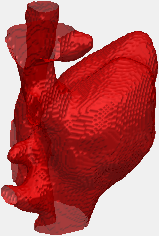

Der plötzliche Herztod ist heutzutage immer noch eine der häufigsten Todesursachen weltweit. Aus diesem Grund bemüht sich die medizinische Bildgebung möglichst genaue Diagnosen zu treffen, um den Patienten eine optimale Therapie zum richtigen Zeitpunkt anbieten zu können. Ein häufig herangezogener Indikator für Herzprobleme ist die sogenannte Ejektionsfraktion, die sich aus dem Pumpvolumen des Herzens bestimmen lässt. Sie sagt etwas über die Leistungsfähigkeit des Herzmuskels aus und ist wichtiger Parameter vieler Standarduntersuchungen. Zur Bestimmung der Ejektionsfraktion in MRT Daten muss ein Arzt manuell die Innenkontur des linken Ventrikels zu verschiedenen Zeitpunkten markieren. Dies ist eine umständliche und zeitintensive Arbeit, die man nach Möglichkeit automatisieren will. In diesem Projekt soll eine einsatzfähige Software für die klinische Forschung etabliert werden, die eine (semi-)automatische Segmentierung des Herzens aus MRT Daten ermöglicht (siehe Abbildung).

Der plötzliche Herztod ist heutzutage immer noch eine der häufigsten Todesursachen weltweit. Aus diesem Grund bemüht sich die medizinische Bildgebung möglichst genaue Diagnosen zu treffen, um den Patienten eine optimale Therapie zum richtigen Zeitpunkt anbieten zu können. Ein häufig herangezogener Indikator für Herzprobleme ist die sogenannte Ejektionsfraktion, die sich aus dem Pumpvolumen des Herzens bestimmen lässt. Sie sagt etwas über die Leistungsfähigkeit des Herzmuskels aus und ist wichtiger Parameter vieler Standarduntersuchungen. Zur Bestimmung der Ejektionsfraktion in MRT Daten muss ein Arzt manuell die Innenkontur des linken Ventrikels zu verschiedenen Zeitpunkten markieren. Dies ist eine umständliche und zeitintensive Arbeit, die man nach Möglichkeit automatisieren will. In diesem Projekt soll eine einsatzfähige Software für die klinische Forschung etabliert werden, die eine (semi-)automatische Segmentierung des Herzens aus MRT Daten ermöglicht (siehe Abbildung).